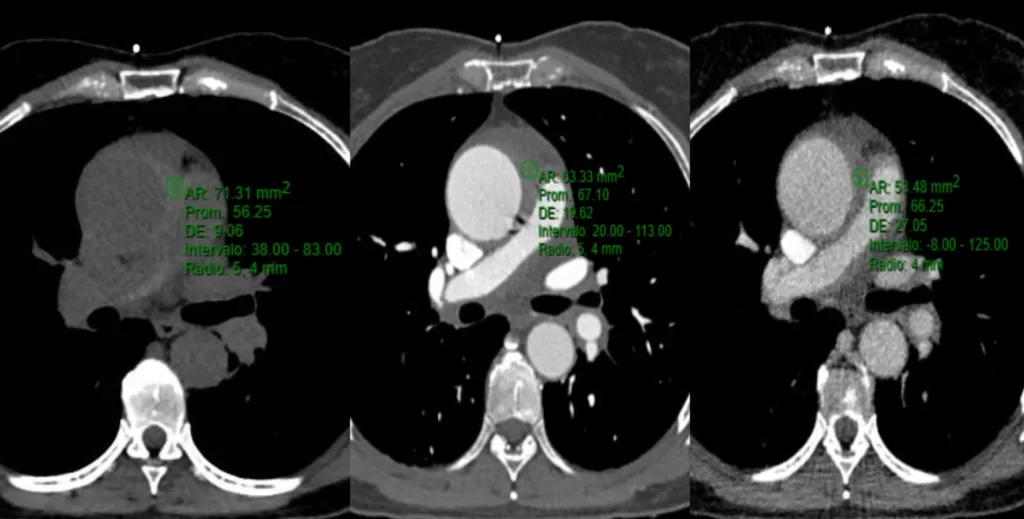

AngioTomografia de Tórax